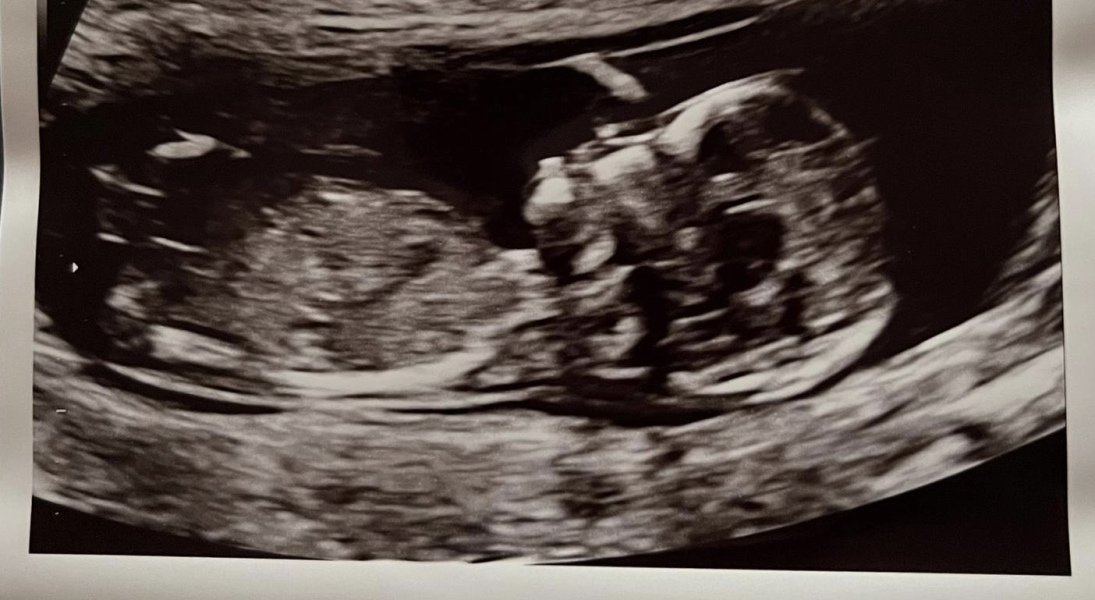

EKnaring · 07/04/2024 11:38

Hey everyone!! My EDD is 25th of September!! I’m so excited to find out the sex if they can tell us at the NHS 20 week scan! Lots think it’s a boy and the skull theory seems to agree but some think the nub says girl - any guesses? The scan photo was from 13weeks 6 days ❤